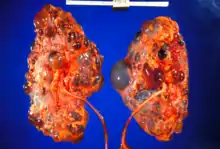

Renal pathology

Renal pathology is a subspecialty of anatomic pathology that deals with the diagnosis and characterization of disease of the kidneys. In a medical setting, renal pathologists work closely with nephrologists and transplant surgeons, who typically obtain diagnostic specimens via percutaneous renal biopsy. The renal pathologist must synthesize findings from traditional microscope histology, electron microscopy, and immunofluorescence to obtain a definitive diagnosis. Medical renal diseases may affect the glomerulus, the tubules and interstitium, the vessels, or a combination of these compartments.